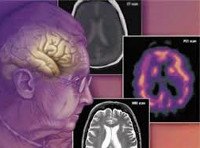

Деменция - приобретенное психическое расстройство, проявляющееся снижением интеллекта и нарушающее социальную адаптацию больного (делает его неспособным к профессиональной деятельности, ограничивается возможность самообслуживания) и не сопровождающееся нарушением сознания. Интеллектуальный дефект при деменции характеризуется комплексным расстройством нескольких когнитивных (познавательных) функций, таких как память, внимание, речь, гнозис, праксис, мышление, способность планировать, принимать решение, контролировать свои действия. В отличие от умственной отсталости, при которой расстройства отмечаются с рождения, деменция развивается при приобретенных органических поражениях головного мозга. К деменции также не относят изолированные нарушения отдельных когнитивных функций (афазию, амнезию, агнозию и ), при которых интеллект как таковой существенно не страдает.

Сосудистая деменция составляет 15-20% всех случаев деменции и является второй по частоте в странах Западной Европы и США. Но в некоторых странах мира, таких как Россия, Финляндия, Китай и Япония, сосудистая деменция занимает 1-е место и встречается чаще, чем болезнь Альцгеймера. В 20% случаев сосудистой деменции напоминает по течению болезнь Альцгеймера, а в 10-20% случаев имеется их сочетание. Современные фундаментальные исследования свидетельствуют о том, что сосудистая мозговая недостаточность является одним из немаловажных факторов патогенеза болезни Альцгеймера. Риск возникновения болезни Альцгеймера и темп прогрессирования когнитивных нарушений, связанных с этим заболеванием, выше при наличии сердечно-сосудистой патологии, например атеросклероза церебральных артерий и гипертонической болезни. С другой стороны, связанные с болезнью Альцгеймера отложения b амилоида в сосудистой стенке могут приводить к развитию амилоидной микроангиопатии, которая усугубляет недостаточность кровоснабжения мозга. Таким образом, основные формы деменции (болезнь Альцгеймера и сосудистая деменция), по современным представлениям, являются патогенетически весьма тесно связанными между собой.